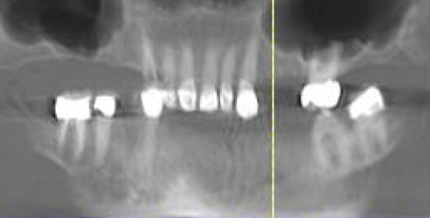

Interceptive implant therapy may then become a consideration earlier in life to create restorations that will not be subject to the latent effect of dental caries as aging continues. An example is shown in Figure 6 and Figure 7; the panoramic film of a 56-year-old man shows several orthognathic and extensive dental procedures historically. All full-coverage restorations had been replaced for a second time, and, again, all evidenced recurrent caries, but the existing dentition was periodontally sound and relatively esthetic.

Fig 6. Panoramic radiograph of 56-year-old patient illustrating a number of dental procedures historically.

Figure 6

Fig 7. Existing dentition was sound periodontally and reasonably esthetic.

Figure 7